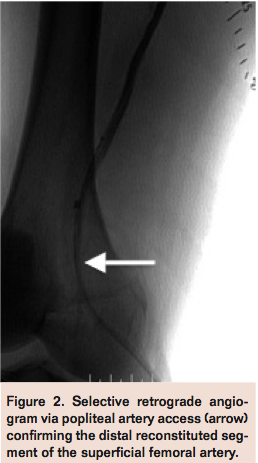

Next, the right popliteal artery was accessed using ultrasound guidance with a micropuncture access kit and a 2.9 French pedal access kit sheath (Cook Medical) (Figure 2) to define the distal occlusion cap by angiography. A SurePath guidewire (IDEV) was advanced in retrograde fashion up to the proximal SFA but entered a subintimal plane adjacent to the true lumen and was again unsuccessful in entering the true lumen secondary to heavy calcification. An Outback re-entry catheter (Cordis) was then advanced over the SurePath guidewire in the subintimal plane to the proximal superficial femoral artery (Figure 3).